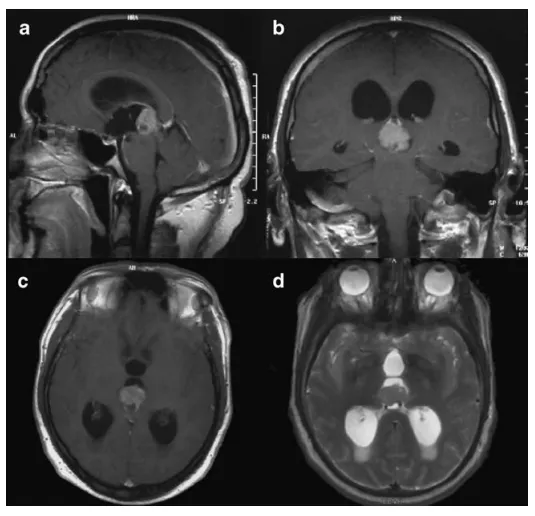

图1 术前矢状位(a)、冠状位(b)及轴位(c)对比增强T1加权磁共振成像;肿瘤在T2加权成像上呈高信号(d)

随后进行了磁共振波谱成像检查,结果高度提示为神经元起源的高度恶性肿瘤,例如高级别室管膜瘤。由于缺少脂质峰,生殖细胞瘤的可能性被排除。综合患者年龄和肿瘤位置来看,松果体实质肿瘤的可能性似乎也不大。